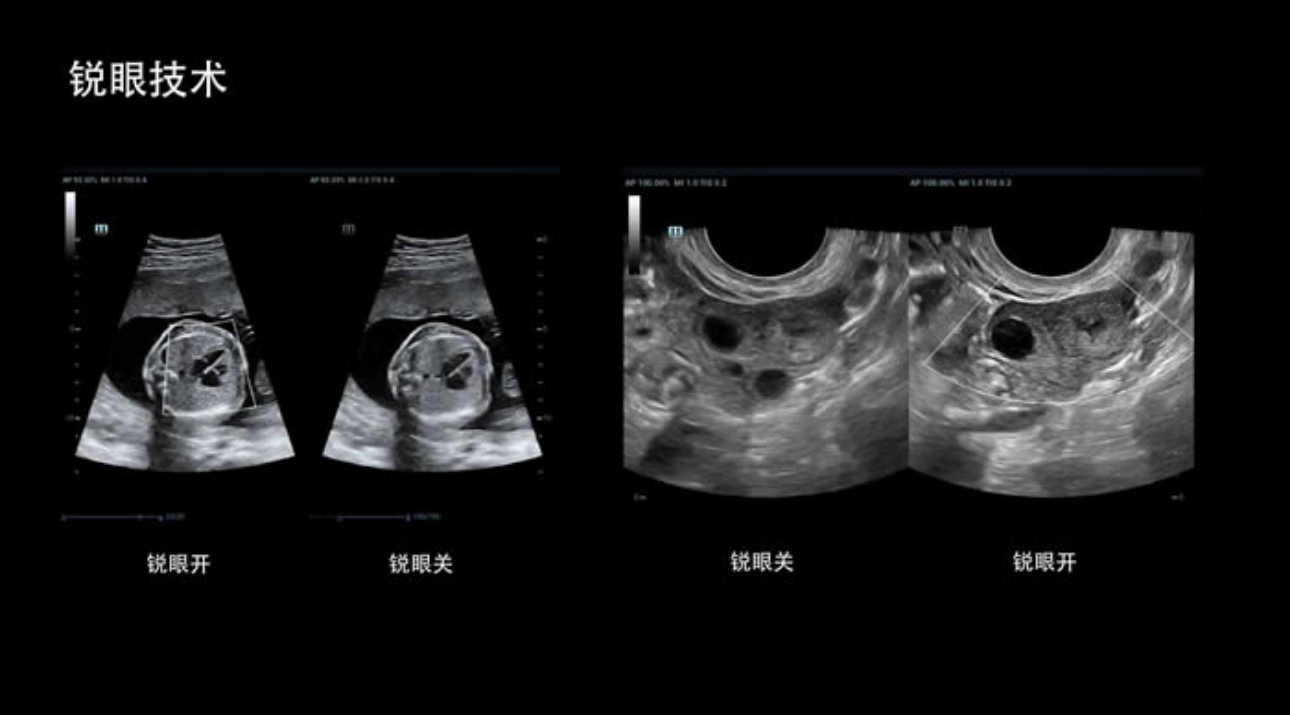

· 锐眼技术

做胎儿心脏检查的时候,如果是声窗不好的孕妇,很难看清胎儿心腔 。女娲Resona 8的锐眼技术能很好的优化心腔内的噪声,让胎心结构清晰的呈现。

锐眼技术